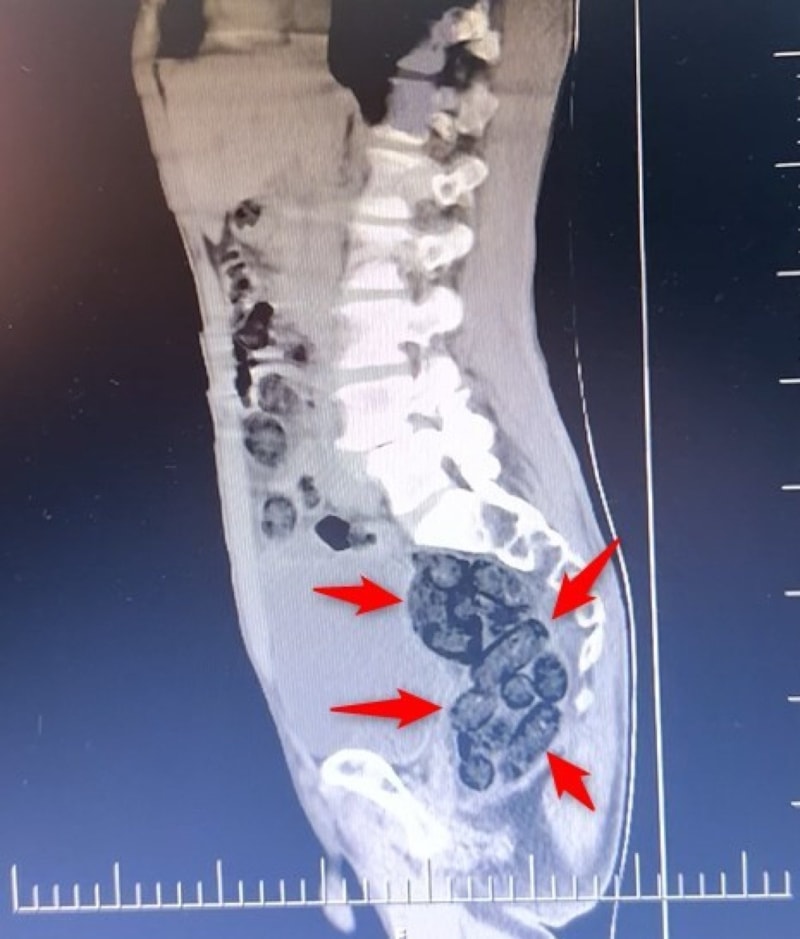

Yapılan incelemeler sonucunda yabancı uyruklu şahsın midesinde, 64 parça halinde toplam 472 gram uyuşturucu maddesi metamfetamin olduğu belirlendi.

Gözaltına alınan şahsın midesindeki uyuşturucu madde çıkartıldı.